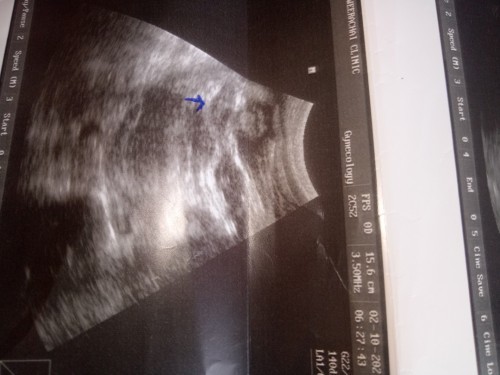

แม่ๆคนไหนพอจะดูออกบ้างว่าเพศหญิงหรือชายค่ะ

เพศหญิงหรือชายค่ะ

ดูไม่ออกเลยค่ะว่าส่วนไหน